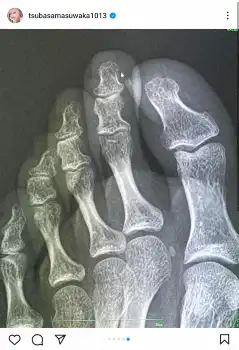

「あまりの痛さに『まさかまた骨折れたのか、、!』と次の日病院に行ってレントゲン撮ったんだけど、綺麗にくっついてました笑」と続け、レントゲン写真を公開した。

また「折れてない!よかったーー!!」と安堵しつつも、「調べたら世の中そのくらいで折れることもあるらしい。くしゃみでも骨折れる人いるらしいね。そんな経験ある人いる?骨折してから骨の大切さが身に染みます。お身体大切に、、」と労った。